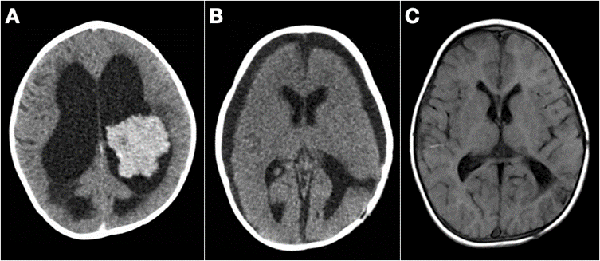

La resección parcial predominó en los grupos 1 (16 casos) y 2 (13 casos). De los 38 pacientes en los que se realizaron resecciones parciales 22 fueron lesiones supratentoriales, entre los cuales se encontraron 8 lesiones centro encefálicas (5 astrocitomas pilocíticos y pilomixoides, 1 craneofaringioma, 1 tumor embrionario indiferenciado y 1 hamartoma hipotalámico), 7 tumores de plexos coroideos (6 papilomas y 1 carcinoma de plexos coroideos) y 7 tumores hemisféricos. Por otro lado, 16 fueron lesiones infratentoriales (6 meduloblastomas, 3 teratoides rabdoides atípicos, 2 ependimomas anaplásicos, 3 astrocitomas pilocíticos, 1 pineoblastoma y 1 carcinoma de plexos coroideos). En la Figura 1 se muestran dos casos de abordajes a estos tumores.

Se realizó biopsia en 3 lesiones de tronco cerebral, 1 lesión pineal abordada endoscópicamente, 1 lesión hipotalámico-quiasmática, 1 lesión frontal subcortical y 1 lesión centroencefálica extensa. En los dos últimos casos se efectuó sólo biopsia por el intenso sangrado que obligó a suspender el procedimiento. El diagnóstico histológico fue tumor embrionario en ambos, por lo que se trataron con quimioterapia (Figura 5-B).

Figura 1: Imágenes intra quirúrgicas de abordajes a tumores en SNC. A) Lesión sólido-quística cerebelosa hemisférica derecha, anatomía patológica: astrocitoma pilocítico. B) Lesión supratentorial intraventricular izquierda, anatomía patológica: papiloma de plexos coroideos.